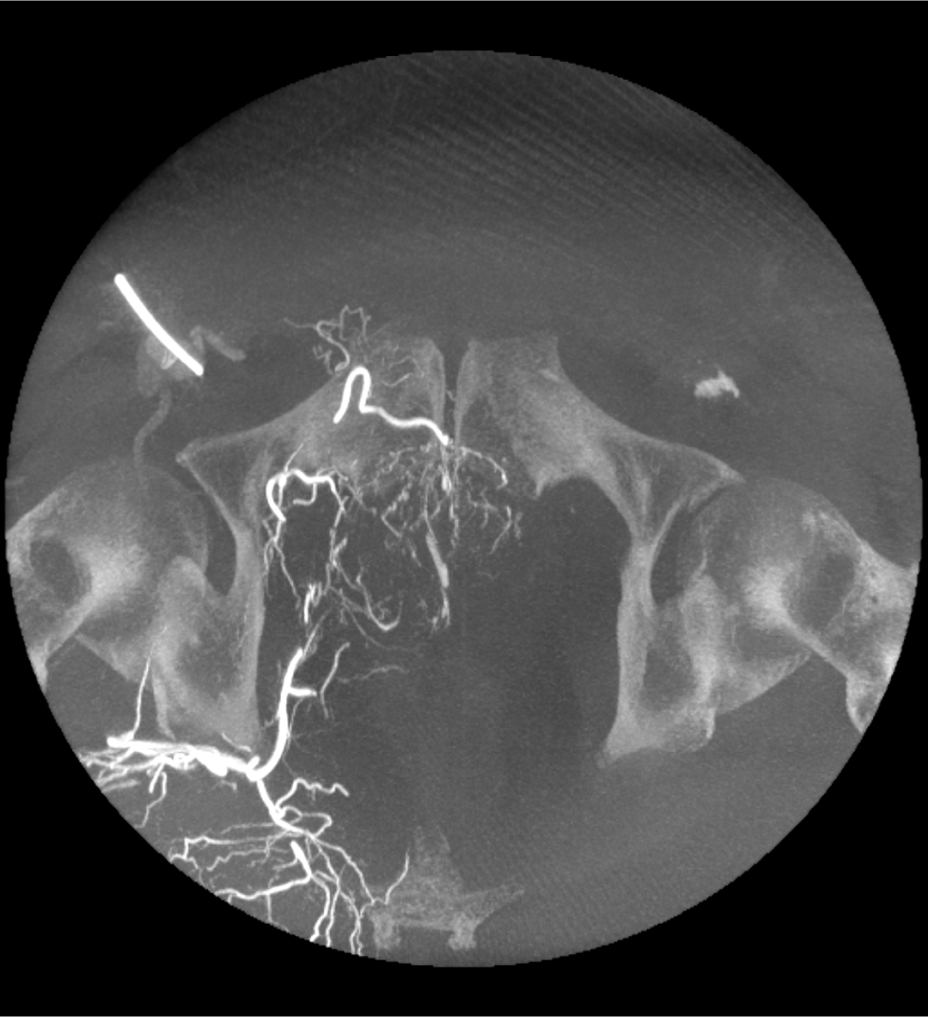

3D CT HD5

Optimisez le diagnostic, la planification de l’intervention chirurgicale, les procédures interventionnelles et le suivi du traitement.

3D CT HD5 est une option basée sur des algorithmes avancés qui améliorent la visualisation des tissus mous, réduisent le bruit et minimisent les artefacts susceptibles de nuire au confort de visualisation. Elle fournit des images de haute qualité des structures internes du corps, notamment les vaisseaux, les os et les tissus mous. Cette fonctionnalité permet aux médecins d’accéder à des images de haute qualité afin de prendre des décisions éclairées en toute confiance.